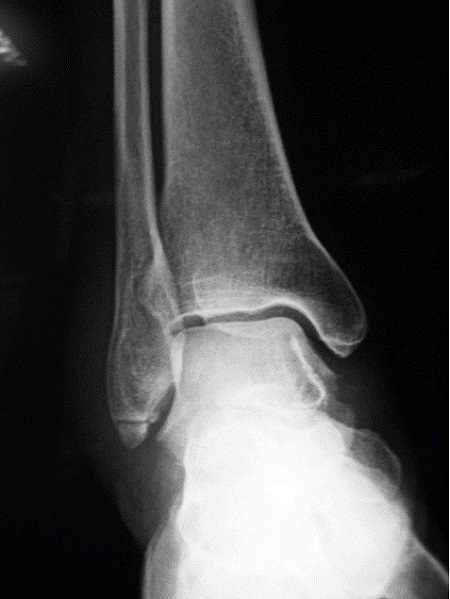

Niña de 11 años de edad sin antecedentes de interés que acude a Urgencias por dolor a nivel del maléolo externo del miembro inferior derecho tras un movimiento anómalo del pie con inversión del tobillo hace 2 días. Asocia tumefacción e impotencia funcional leves. Le han administrado analgesia en el domicilio sin mejoría. A la exploración, presenta tumefacción y dolor selectivo a la palpación del maléolo externo y los ligamentos peroneoastragalinos anterior y posterior. No crepitación ni resaltes óseos ni hematoma. No presenta limitación de la movilidad pasiva y si presenta limitación a la movilización activa por dolor. Se realiza radiografía anteroposterior (Figura 1) y lateral (Figura 2) del tobillo derecho.

Figura 1. Proyección anteroposterior.